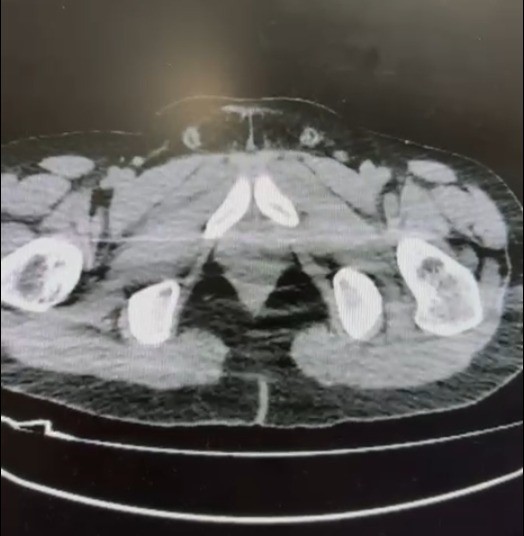

Nevşehir İl Emniyet Müdürlüğü Narkotik Suçlarla Mücadele Şube Müdürlüğü ekipleri, kentte uyuşturucu ve uyarıcı madde ticareti yapmak ve kullanmak suretiyle vatandaşları zehirleyen sokak satıcılarına yönelik çalışma başlattı. Cumhuriyet Başsavcılığı koordinesinde çalışmalarını yoğunlaştıran ekipler, şüpheliler S.B. ve O.R.’nin ’yutma yöntemi’ ile kente uyuşturucu madde sevk edeceği bilgisi üzerine operasyon düzenledi. Şüphelilerin ikametlerinde ve araçlarında yapılan aramada 101 kapsül halinde 722 gram uyuşturucu madde, 1 adet hassas terazi, uyuşturucu madde sevkiyatında yutma yönteminde kullanılan muhtelif materyaller, uyuşturucu madde ticaretinden elde edilen 20 bin 210 TL, bin 320 euro ve 10 ABD doları ele geçirildi. Emniyetteki işlemlerinin ardından adliyeye sevk edilen 2 şüpheli, çıkarıldıkları mahkemece tutuklanarak cezaevine gönderildi.